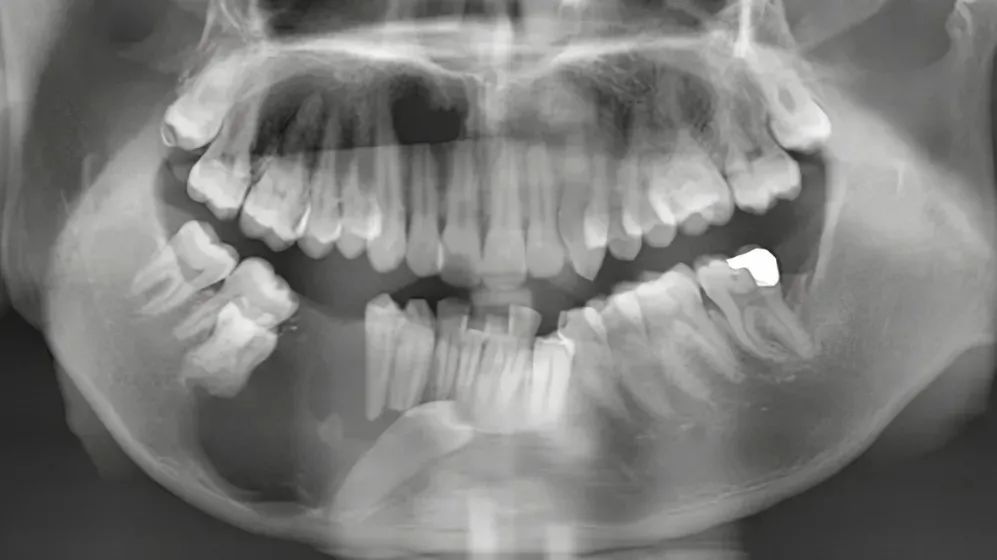

▲标记处为:儿童换牙期缺失牙,乳牙脱落后则会缺牙。